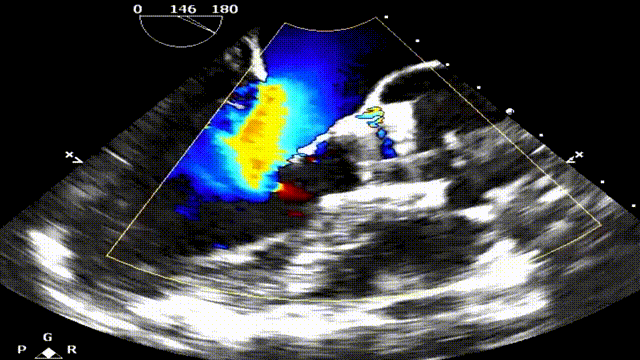

台上复查食道超声,瓣架圆形展开,启闭良好:

食道超声瓣架位置正确,启闭良好,未见明显瓣周漏: